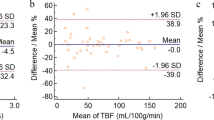

Interobserver agreement was excellent for all quantitative measurements (Table 1). The Bland–Altman analyses showed relatively small bias and 95% limits of agreement for each quantitative parameter (Table 1).

No significant difference was observed between BTs and MTs for any parameter (all p > 0.05). PAs demonstrated significantly higher T1, T2, PD, and ADC values than WTs (all p < 0.001). To differentiate PAs from WAs, AUC values for T1, T2, PD, and ADC were 1.000 with 95% CI of 0.872–1.000, 1.000 with 95% CI of 0.872–1.000, 0.928 with 95% CI of 0.760–0.991, and 1.000 with 95% CI of 0.872–1.000, and the optimal threshold values were ≤ 1317 ms, ≤ 69 ms, ≤ 78%, and ≤ 1.033 × 10−3 mm2/s, respectively. Compared to MTs, PAs had significantly higher T1, T2, and ADC values (all p < 0.001), whereas WTs had significantly lower T1, T2, and PD values (p < 0.001, p = 0.008, and p = 0.003, respectively) (Table 2). T2 and ADC values performed the best in differentiating between MTs and PAs (AUC = 0.928 with 95% CI of 0.740–0.994 and 0.939 with 95% CI of 0.756–0.996, respectively). T1 and PD values performed the best in differentiating between MTs and WTs (AUC = 0.915 with 95% CI of 0.738–0.988 and 0.833 with 95% CI of 0.638–0.949, respectively) (Fig. 1). The T1, T2, PD, and ADC values for each tumor type are plotted in Fig. 2. PAs typically had high T1, T2, PD, and ADC values; in contrast, WTs had low T1, T2, PD, and ADC values. Most MTs had lower T2 and ADC values compared to PAs, and higher T1 and PD values compared to WTs.

Receiver-operating characteristic (ROC) curves of T1, T2, PD, and ADC values for differentiating malignant tumors (MTs) from pleomorphic adenomas (PAs) (a) and Warthin tumors (WTs) (b). In differentiating MTs from PAs, area under the ROC curve (AUC) values for T1, T2, PD, and ADC were 0.894, 0.928, 0.716, and 0.939, respectively. In differentiating MTs from WTs, AUCs for T1, T2, PD, and ADC were 0.915, 0.806, 0.833, and 0.600, respectively